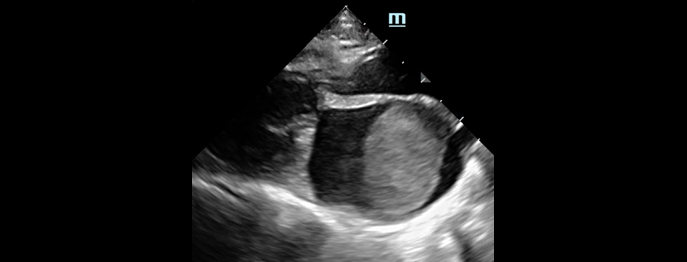

Im zweiten Teil erlernen Sie die Durchführung des kardialen-POCUS sowie des Lungen-POCUS